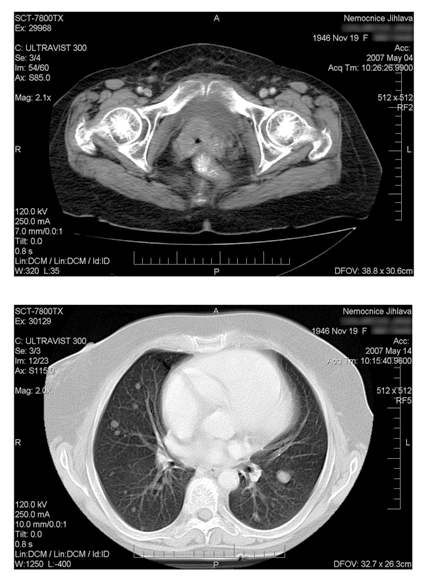

Histologicky šlo o epidermoidní karcinom. V dubnu 2007 vysloveno na

vaginálním UZV podezření na lokální recidivu. V květnu 2007

potvrzena lokální recidiva v pánvi a navíc zjištěny mnohočetné

metastázy do plic.

Pacientka zahájila chemoterapii režimem CDDP +

topotecan v dávkování CDDP 50 mg/m2 1.den a topotecan

0,75 mg/m2 1.-3.den s intervalem 3 týdnů. Po. 4.cyklu v

srpnu 2007 byla provedena kontrolní CT vyšetření a bylo zjištěno

úplné vymizení všech metastáz na plicích. Podobně vymizel i

patologický nález v malé pánvi. Po podání 5 cyklu byla léčba

ukončena.